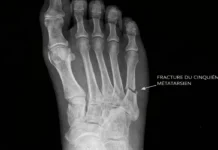

Une fracture du pied, notamment une fracture de fatigue du premier métatarsien, peut se présenter avec une douleur aiguë, un gonflement localisé et une boiterie. En l’absence de traumatisme évident, ces douleurs peuvent être confondues avec une poussée douloureuse d’un hallux valgus évolué. L’imagerie est alors indispensable.

Signes radiographiques de l’hallux valgus

La radiographie du pied constitue l’examen de référence pour confirmer le diagnostic d’hallux valgus et évaluer l’importance de la déformation. Elle permet une visualisation précise de la structure osseuse, des axes articulaires et des éventuelles complications associées. Réalisée en charge, elle reproduit les conditions réelles d’appui du pied, ce qui est essentiel pour mesurer les désalignements dynamiques.

L’un des principaux critères d’analyse est l’angle métatarsien (angle IM), formé entre l’axe du premier et du deuxième métatarsien. Cet angle est normalement inférieur à 9°. Lorsqu’il dépasse ce seuil, cela témoigne d’un écartement excessif des deux métatarsiens, signalant une instabilité du premier rayon. Plus cet angle est grand, plus la déformation est avancée.

Le second paramètre fondamental est l’angle d’hallux valgus (angle HV), qui mesure l’écart entre l’axe du premier métatarsien et celui de la phalange proximale du gros orteil. Un angle supérieur à 15° indique une déviation pathologique. Les angles modérés se situent entre 15 et 30°, tandis que les formes sévères dépassent 40°.

Les radiographies permettent aussi d’évaluer le positionnement des os sésamoïdes, petits os situés sous la tête du premier métatarsien. En cas d’hallux valgus, ces os ont tendance à se déplacer latéralement avec la phalange, perdant leur alignement avec le métatarsien. Leur déplacement est un marqueur de gravité, car il perturbe la biomécanique de l’avant-pied et contribue à l’instabilité articulaire.

L’imagerie permet également de détecter une exostose médiale (la bosse osseuse caractéristique), qui correspond à une hypertrophie de la tête du premier métatarsien. Cette excroissance est fréquemment en conflit avec les chaussures, ce qui explique les douleurs localisées et les bursites associées.

En parallèle, on peut observer une ostéoarthrose de l’articulation métatarsophalangienne, surtout dans les formes évoluées ou anciennes. Elle se manifeste par un pincement de l’interligne articulaire, des ostéophytes marginaux, et parfois une sclérose sous-chondrale. Ces signes radiographiques sont importants à prendre en compte, car ils influencent le choix thérapeutique, notamment chirurgical.

En résumé, la radiographie standard du pied en charge offre une cartographie détaillée de l’hallux valgus. Elle permet non seulement de poser un diagnostic de certitude, mais aussi de mesurer la sévérité de la déformation, d’identifier les atteintes associées, et d’orienter les choix thérapeutiques — qu’ils soient conservateurs ou chirurgicaux.